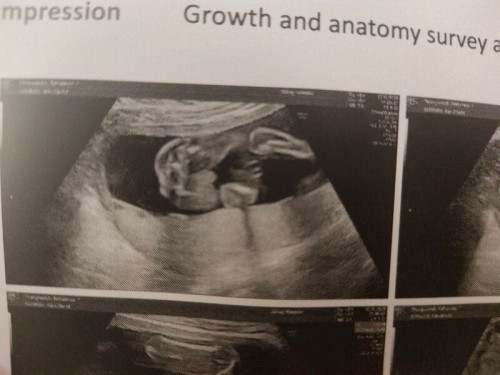

คุณหมอซาวด์แล้วบอกไม่แน่ใจเพราะน้องคว่ำหน้าค่ะ 20+2 w ค่ะ